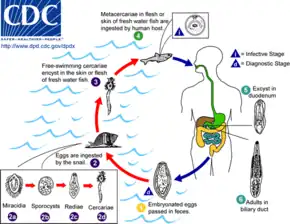

Production of eggs

The eggs of a C. sinensis are released through the biliary tract, and excreted out along with the faeces. The eggs are embryonated and contain the larvae called miracidia. Unlike most other flukes in which the miracidia undergo development and swim in water to infect suitable host, the eggs of C. sinensis are simply deposited in water. The eggs are then eaten by snails.[9]

First intermediate host

Freshwater snail Parafossarulus manchouricus often serves as a first intermediate host for C. sinensis in China, Japan, Korea, and Russia.[11][12] Other snail hosts include Alocinma longicornis Bithynia longicornis, Bithynia fuchsiana, Bithynia misella, Parafossarulus anomalospiralis, Melanoides tuberculata, Semisulcospira cancellata, Koreoleptoxis amurensis, Semisulcospira libertina, and Assiminea lutea in China;[12] and Melanoides tuberculata in Vietnam.[13][14]

Once inside of the snail body, the embryonic membrane is dissolved by the snail's digestive enzymes, so the miracidium hatches from the egg. The ciliated miracidium can move about, penetrating the intestine, and enters the haemocoel and digestive gland. Here, it undergoes metamorphosis into a sporocyst. The sporocyst gives rise to small larvae called rediae. The rediae burst out from the sporocyst to become the next-stage larvae called cercaria. This system of asexual reproduction allows for an exponential multiplication of cercaria individuals from one miracidium. This aids the fluke in reproduction, because it enables the miracidium to capitalize on one-chance occasion of passively being eaten by a snail before the egg dies. The mature cercariae bore out of the snail body into the freshwater environment. However, they are nonfeeding and must find a fish host within 2–3 days, otherwise they die.[9]

The cercariae of C. sinensis are different from those of other flukes in that they do not swim. Instead, they initially hang upside down in the water, and then sink to the bottom. They rise to the water surface to resume their initial position, and the movement is repeated again. They attack fish when they feel any disturbance.[8]

Second intermediate host

When they detect fish, they attach themselves on the scales using their suckers. Boring their way into the fish's body, they penetrate into the fish muscle within 6 to 13 minutes. Within an hour of penetration, they develop hard coverings called cysts and become metacercariae. This protective cyst is useful when the fish muscle is consumed. The metacercariae gradually develop and become infective to their next hosts after 3 to 4 weeks.[8]

The common second intermediate hosts are freshwater fish such as common carp (Cyprinus carpio), grass carp (Ctenopharyngodon idellus), crucian carp (Carassius carassius), goldfish (Carassius auratus), Pseudorasbora parva, Abbottina rivularis, Hemiculter spp., Opsariichthys spp., Rhodeus spp., Sarcocheilichthys spp., Zacco platypus, Nipponocypris temminckii , and pond smelt (Hypomesus olidus).[15] In China, 102 species of fish and four species of shrimp are known to be the intermediate hosts.[14] In Korea, 40 species of freshwater fish are recorded as hosts.[16] Seven species of fish are known as hosts in Russia.[17]

Definitive host

Humans are the major definitive hosts. Infection occurs when raw or undercooked fish contaminated with the metacercariae is eaten. The cysts of the metacercariae are gradually digested by the human gastric acids, and upon reaching the small intestines, the entire cyst is lost. The free metacercariae penetrate the intestinal mucosa and enter the bile ducts. Migration into the bile ducts takes 1–2 days. They start feeding on the bile secreted from the liver, and gradually grow.[10] They become adults in about a month, and start laying eggs. The average lifespan of an adult fluke is 30 years.[8] An individual fluke can produce 4,000 eggs in a day.[18]

Other definitive hosts are fish-eating mammals such as dogs, cats, rats, pigs, badgers, weasels, camels, and buffaloes.[15]